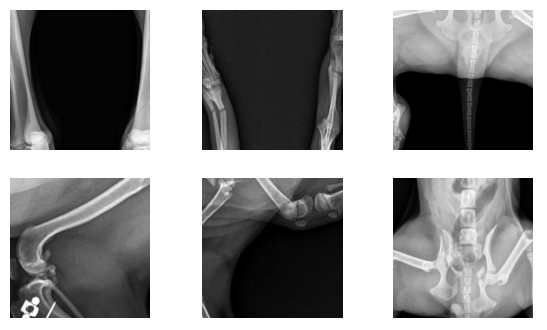

We employ a dual methodology to determine the ideal number of clusters. First, we conduct a systematic sweep over a range of clusters, and use Silhouette Score [50] and Adjusted Rand Index Score [51] to quantitatively evaluate the clustering outcomes. This data-driven approach serves as the first filter in determining the optimal number of clusters. Second, we prioritize interpretability by manually inspecting the images to identify visual features that could serve as natural cluster centers. We aim to ensure that the clusters represent distinct, interpretable categories that reflect the underlying structure of the data. Through this inspection, we identify a set of major visual features that we believe the model should capture. These features include vertical lines, horizontal lines, oblique lines, absence of lines, zoomed-out images, and the presence of medical devices among others.

We ultimately select six clusters. This choice aligns with the major visual features we wish the model to recognize, achieving a balance between optimization and interpretability. Figure 2 showcases a representative sampling of images belonging to each cluster. This categorization helps in understanding the nature of the classifier’s outputs and enriches insights into whether the clusters are being formed based on features that are both interpretable and logically coherent.